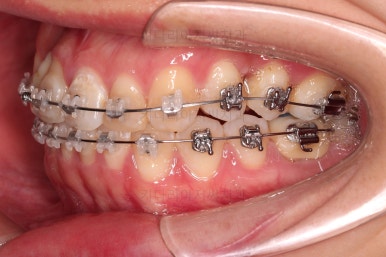

장치를 부착한 모습입니다.

이번 환자분은 자가결찰 세라믹(엠파워 클리어) 장치를 선택하셨고요.

잔존유치는 발치했고, 앞니 가짜치아는 벗겨내고 새로운 가짜치아를 와이어에 묶어주었습니다.